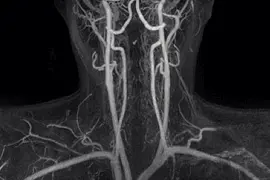

Важливою особливістю шиї є те, що через неї проходять судини, які живлять головний мозок. Це сонна і хребетна артерії. Судини шиї є одним з об’єктів дослідження при МРТ шиї. Обстеження судин шиї, як правило, проводиться разом з судинами голови (МРТ голови і шиї).

На апараті Центру дослідити судини можливо обстежити без введення контрасту. По суті, ці судини є одним цілим і передбачають діагностику судин голови і шиї в одному пакеті.